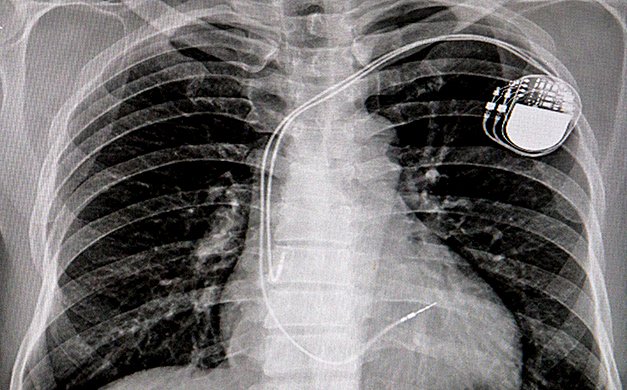

„Consimțământul informat al pacientului" era falsificat. După semnarea de către pacienți, era adăugat, fără ca aceștia să știe, cu un pasaj scris de mână prin care și-ar fi dat acordul pentru pentru implantarea unor dispozitive refolosite.

Scandalul medicilor români cercetați pentru că preluau dispozitive medicale de la cadavre și apoi le montau pacienţilor a atras atenţia presei internaţionale care vorbeşte despre sistemul sanitar medical românesc, măcinat de corupţie.